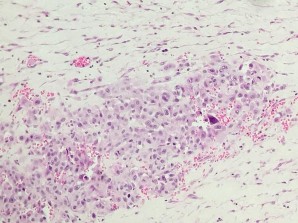

HE x 100: Các tế bào u hình thoi, sắp xếp thành bó | HE x 400: Bào tương tế bào u băt màu hồng, nhân lớn, rõ hạt nhân, nhiều nhân chia |

1. U cơ vân ác tính (Rbahdomyosarcoma) (Bệnh nhân: Phạm Văn T.)